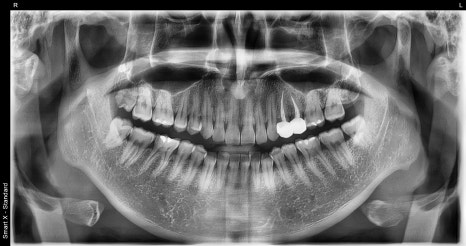

First photo: Initial panoramic image. We checked the overall dental condition and the areas requiring extraction and treatment.

Second photo: Upper molar photo taken at the initial visit. The caries area and the broken tooth condition are visible.

Third photo: Lower molar photo taken at the initial visit. Caries had progressed in two lower molars, and inlay treatment was needed.